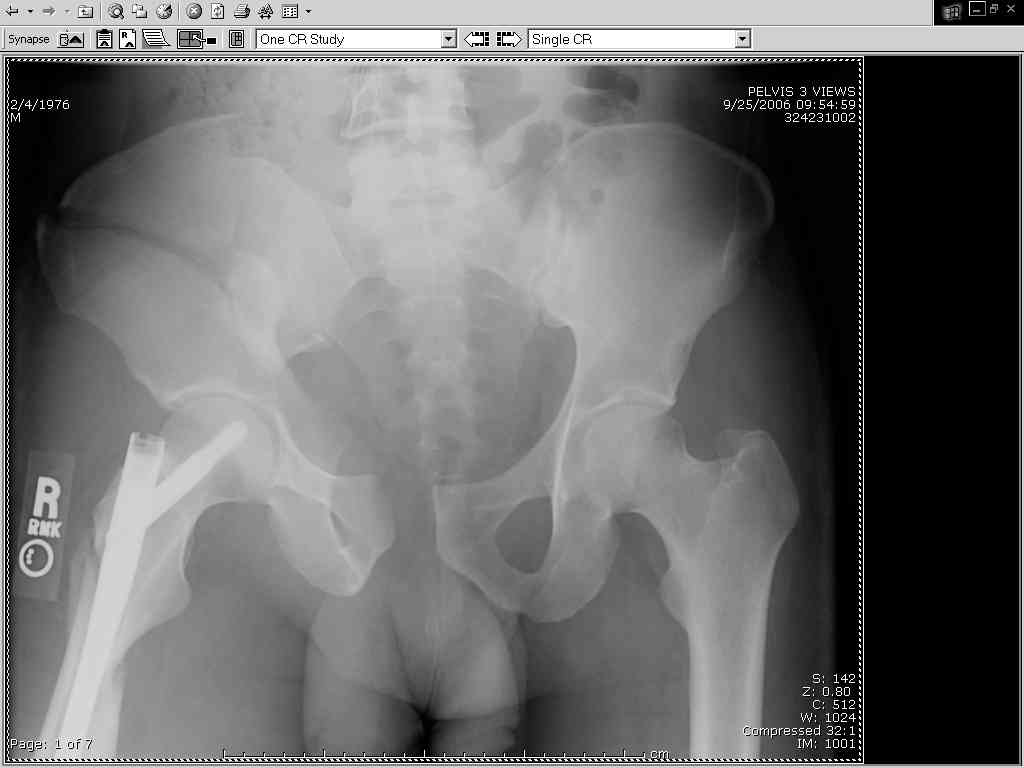

Thanks Adam - I agree it's not a pure APC (is there really such thing as a pure force vector strictly in the x,y or z plane?). I stand corrected. Maybe a hybrid APC (ext rot of L hemipelvis, symphysis disruption, ext rot of R anterior innominate) plus vertical shear as well with 3 or-so cm of cephalad migration of the R ilium. Maybe just "C-type".....

It almost looks to me like an extra-articular both column fx, in addition to the pelvic component. It has the typical triangular fragment and the OO view has a hint of the spur. You may be able to get it all with plates. I would consider fixing the crest first, then a long plate for both symph and iliac portion. SI may close with reduction of symphisis. Looks like the inferior portions are intact. I like your plan as well. You will probably solicit lots of opinion. Good luck. Look forward to post op view.